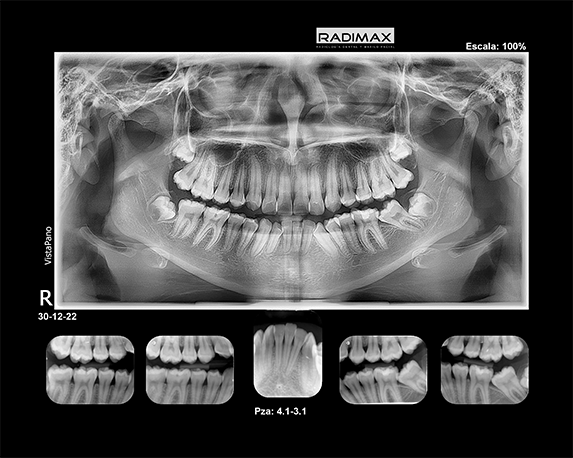

Todas nuestras prestaciones están orientadas a proveer la mejor imagen e informes diagnósticos del territorio Oral y Máxilo Facial, entre las que se cuentas técnicas retroalveolares, radiografías panorámicas, telerradiografías y estudios radiográficos de articulaciones témporo mandibulares (ATM)

Retroalveolar Piezas

Retroalveolar Total

Bite wing Der Izq

Panorámica